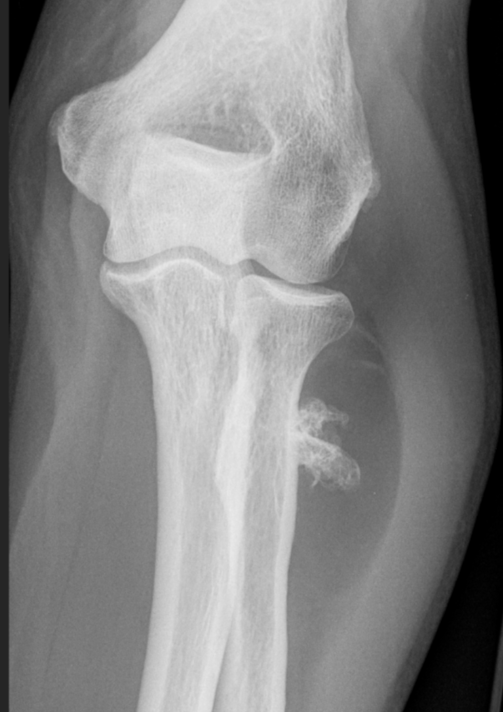

3. Osseous Lipoma